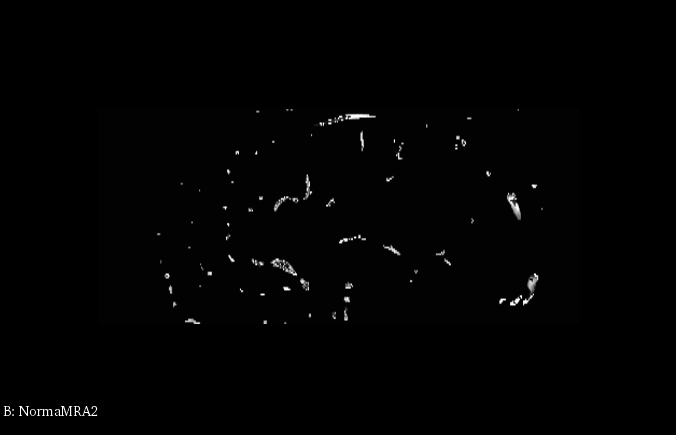

4、血管提取效果

如图所示的第一个图像展示了原始MRA扫描结果(Magnetic Resonance Angiography),其中在颅内可见一束明显的血管结构;第二个图像基于Hessian矩阵处理后得到血管区域分布;通过观察各幅图像效果可以看出该方法在血管定位方面表现较为准确;整体显示良好